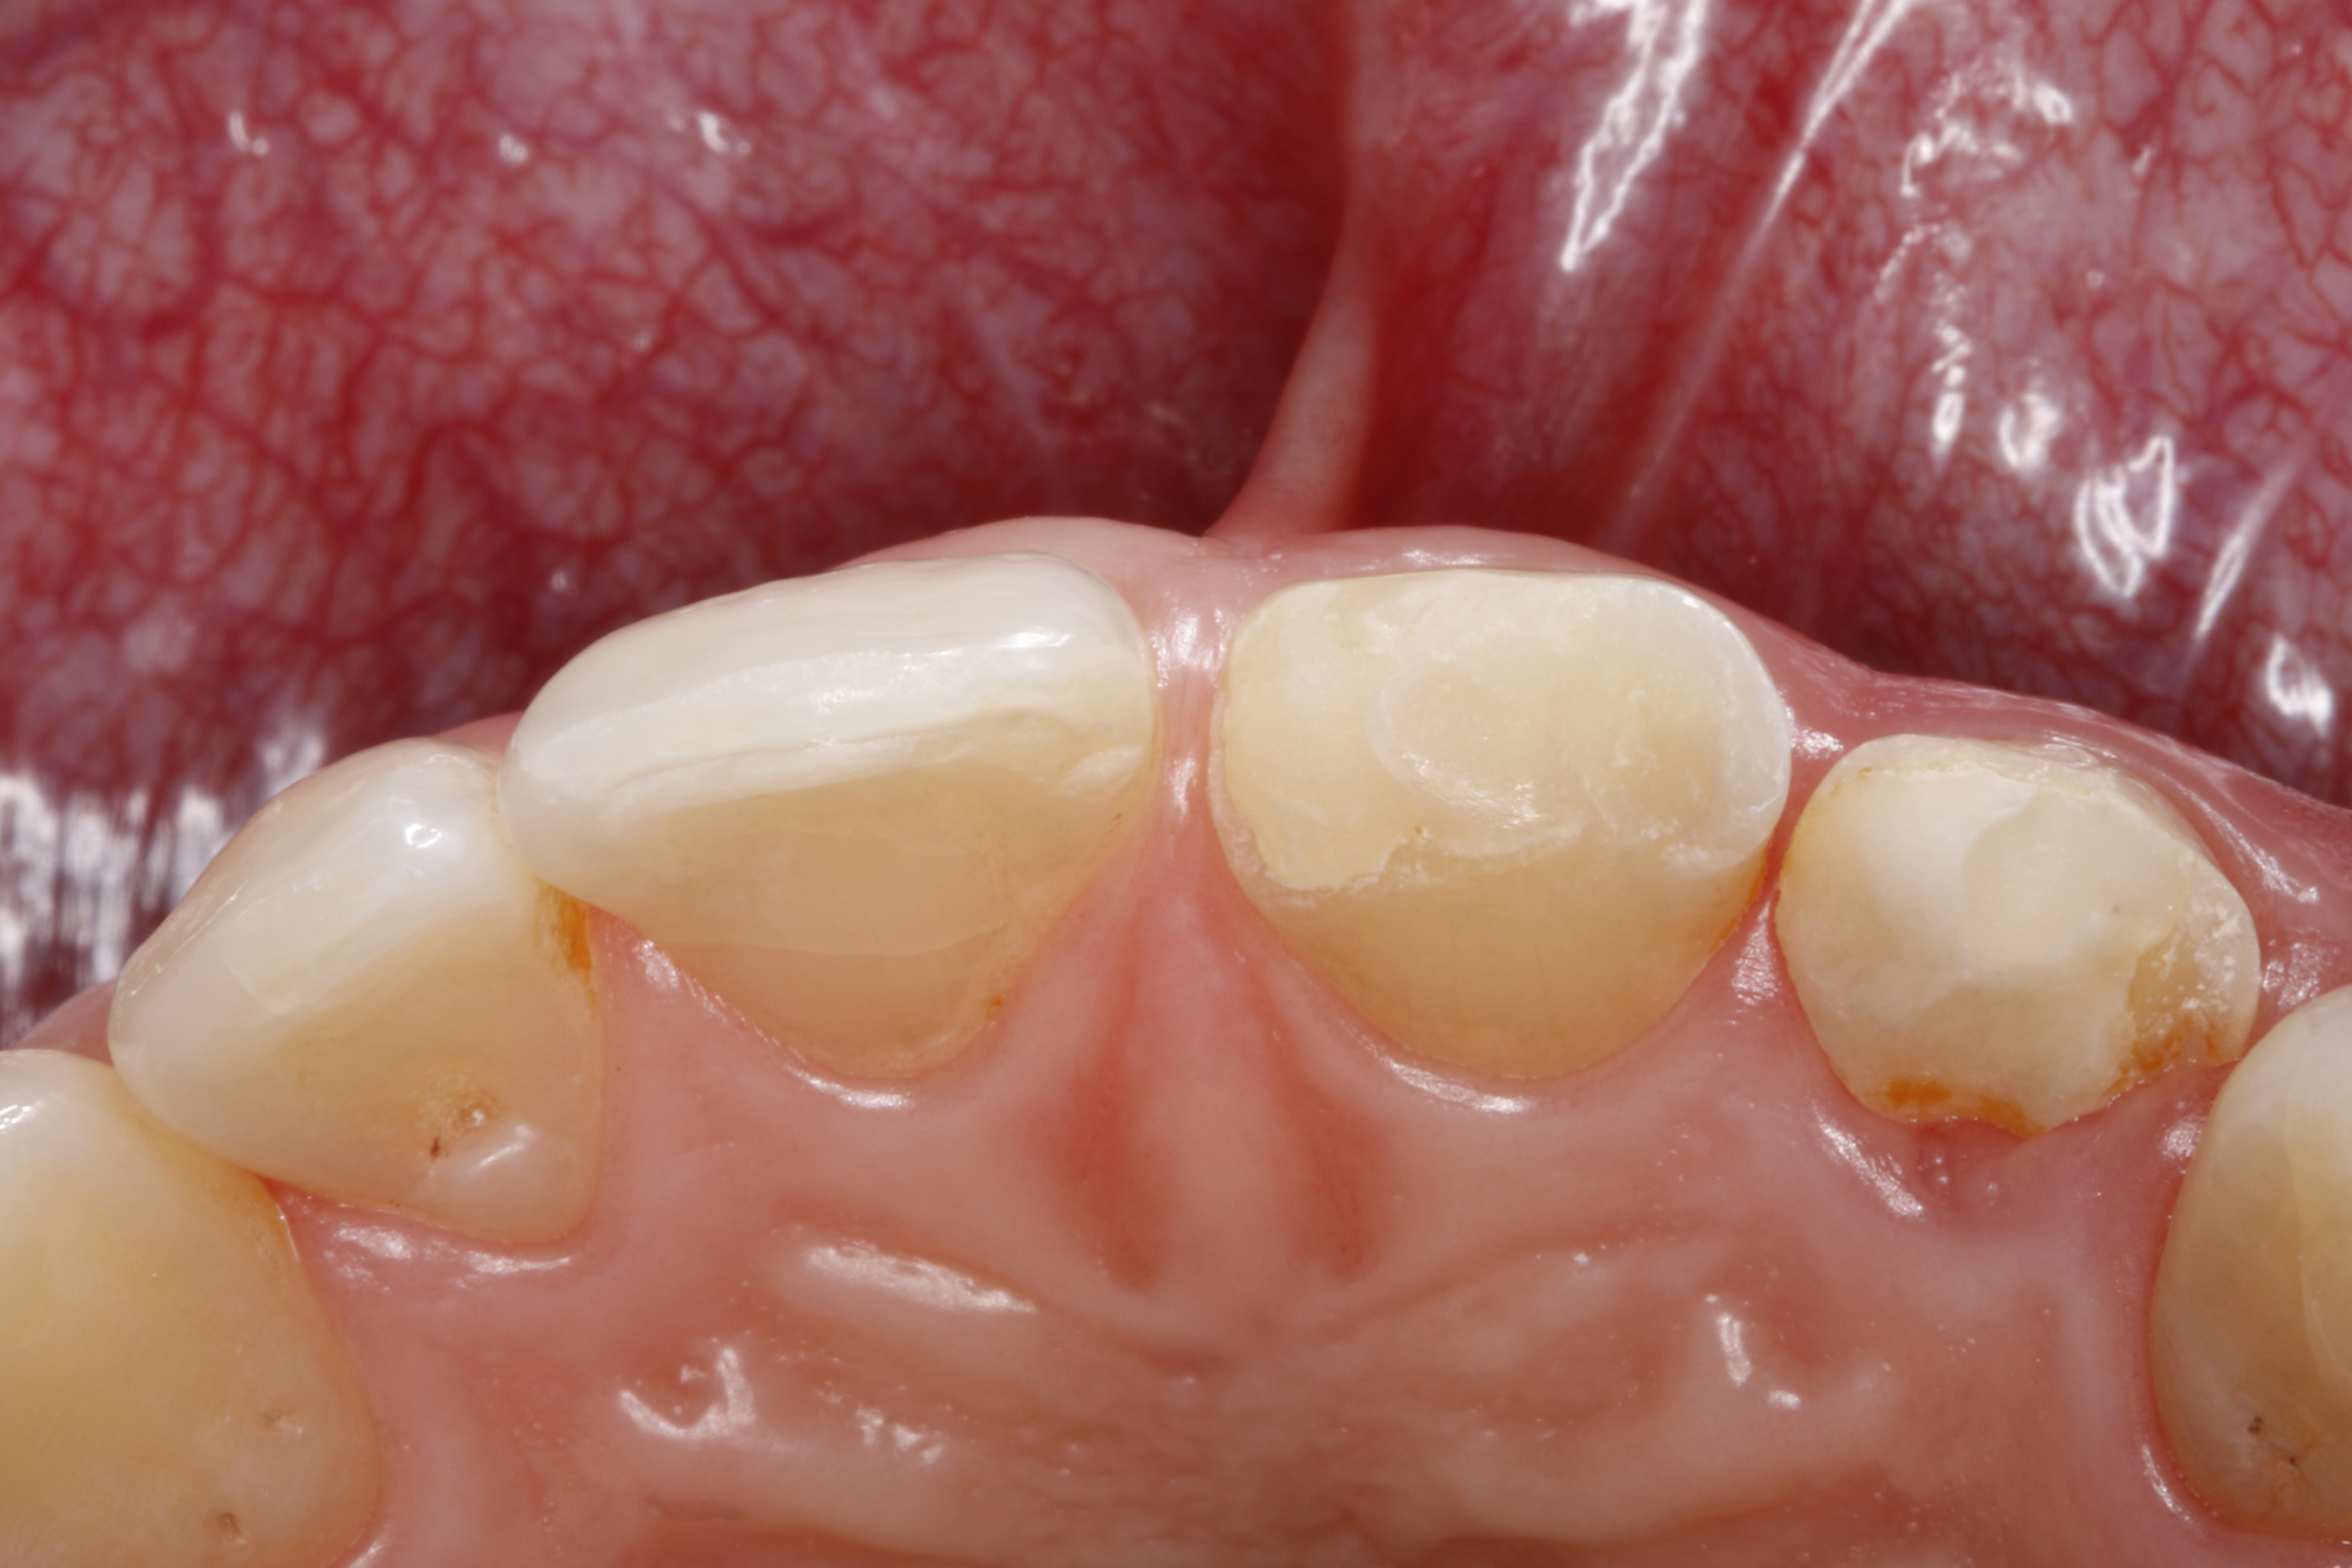

Ryc. 2. Sytuacja początkowa, widok od strony brzegów siecznych – widoczne głębokie, podniebienno‑dystalne złamanie zęba 22, uniemożliwiające odbudowę ze względu na niekorzystny przebieg płaszczyzny złamania. Z tego względu ząb zachowano tylko do czasu zaplanowanego usunięcia z natychmiastowym wszczepieniem implantu.